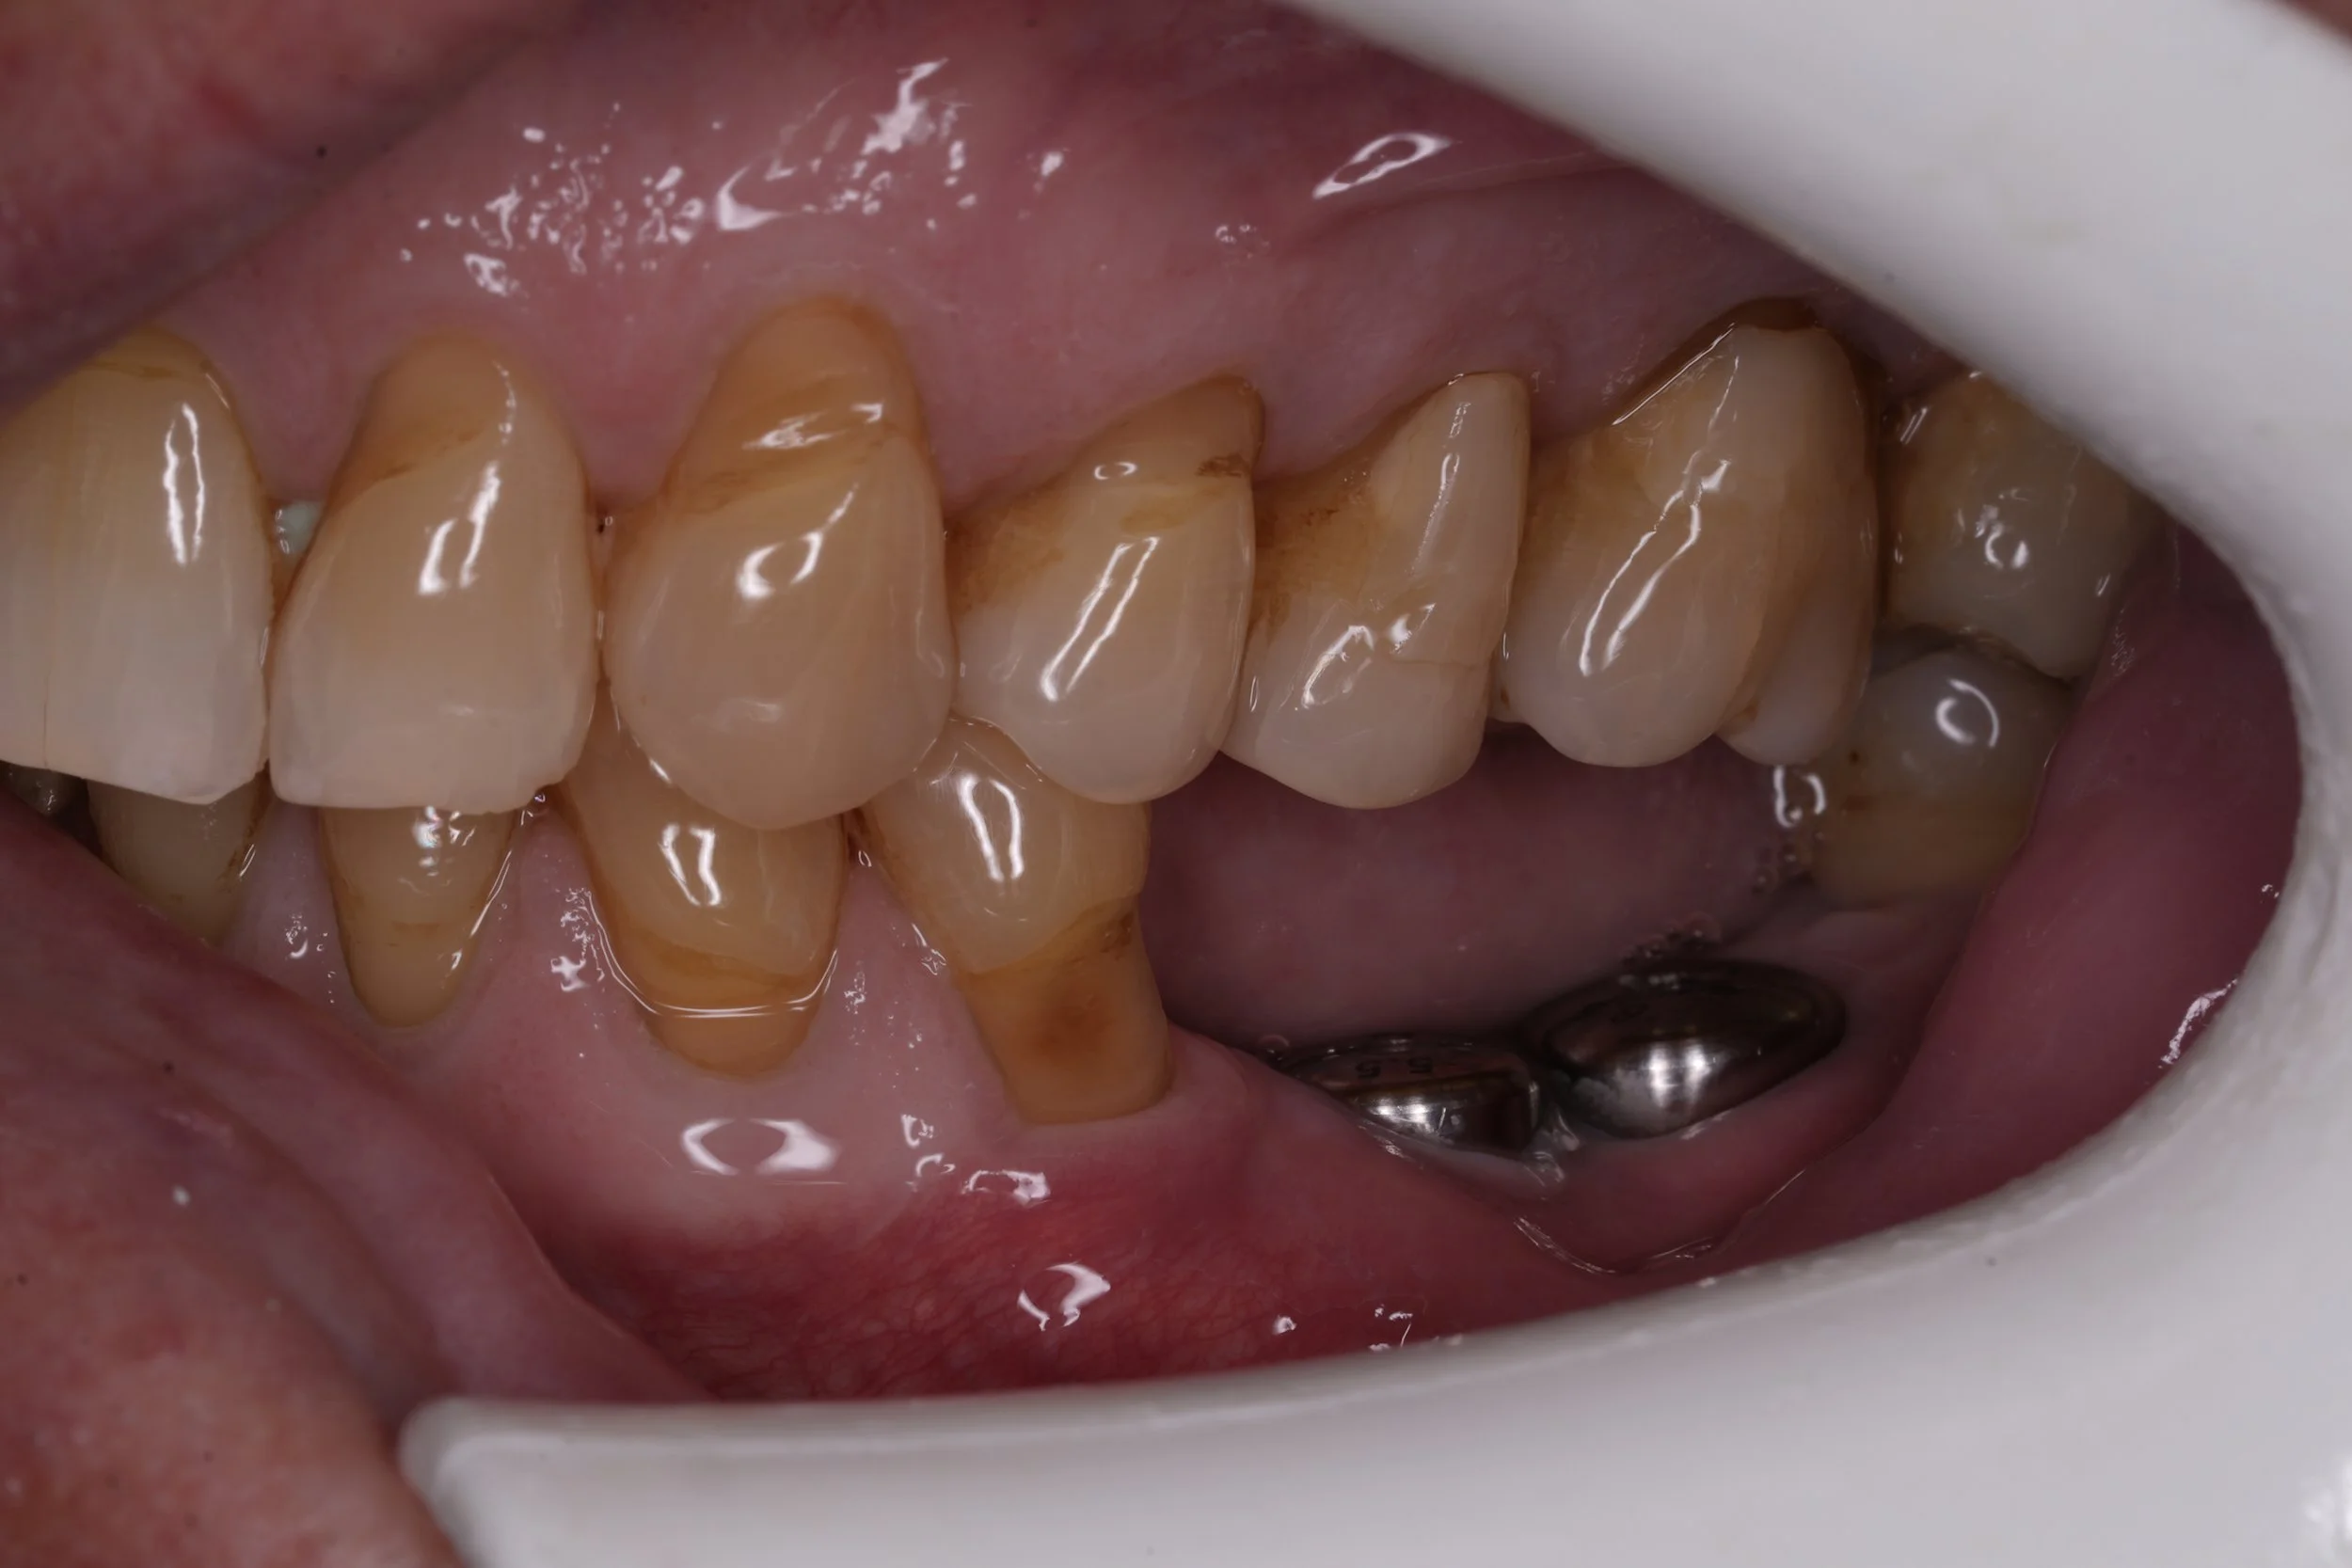

Fixed pros